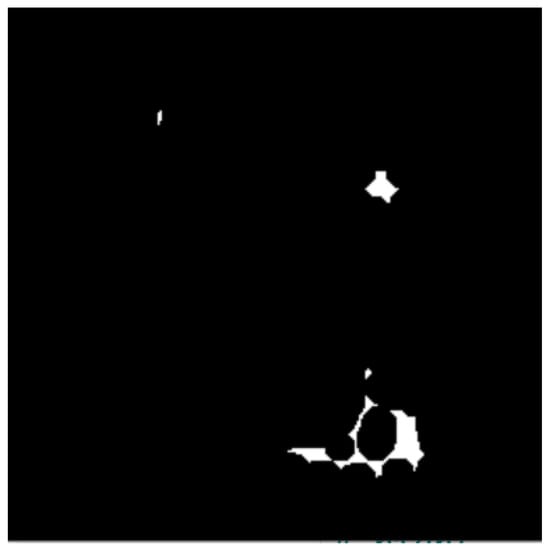

- The active contours method uses the obtained binary masks from the connected components analysis to highlight and isolate the edges/boundaries of ROIs. Further, the blob detection method is used to resolve undersegmentation from the previous step and identify BC lesions (blobs) from the previously obtained masked images.

3.4. Detection